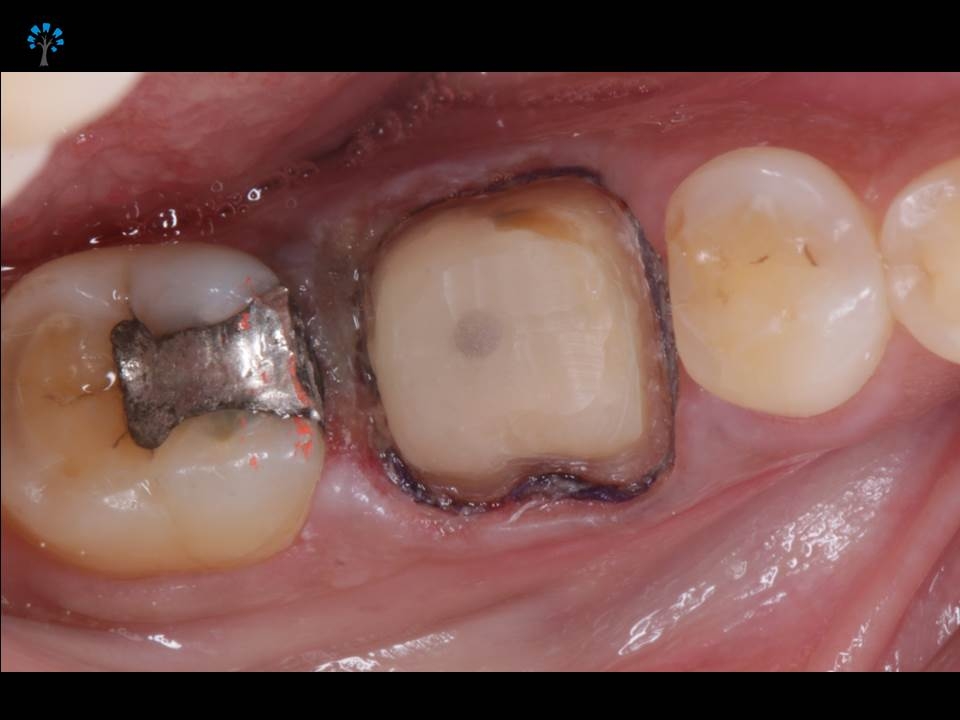

An elderly patient reported with a dislodged gold crown.

Examination revealed fracture of the distal portion of the tooth (Fig 1,4).

PREOPERATIVE VIEW